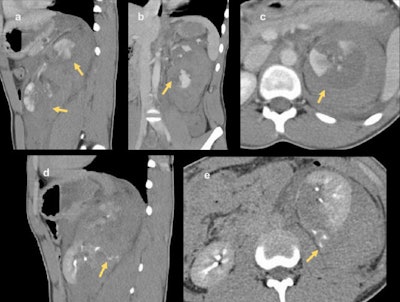

imaging (d) and (e), extravasation of contrast material from the collecting system of the lower pole can be seen. This patient subsequently underwent left nephrectomy.

In cases of penetrating trauma, preliminary noncontrast CT images may be of benefit in identifying and distinguishing extravasation from foreign bodies. If there is suspicion of an injury to the collecting system based on the initial scan, a delayed or excretory phase should be performed after 10 to 20 minutes. Injuries to the collecting system may be indicated on the initial scan by evidence of a laceration that appears to extend to the collecting system or by the presence of perinephric free fluid. Delayed-phase images also are useful in evaluating vascular injuries, such as active bleeding and pseudoaneurysm, the researchers noted.